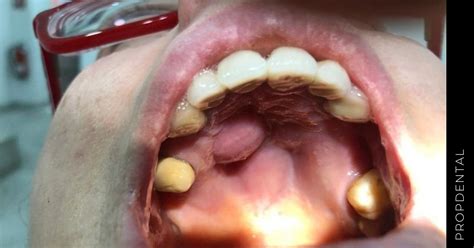

El paladar se encuentra en la parte superior interna de la cavidad bucal, separando la cavidad nasal de la bucal. Se divide en dos partes:

- Paladar Óseo (Duro): La zona más dura formada por huesos.

- Paladar Blando: Recubierto con una capa de mucosa que llega hasta la úvula, impidiendo que la comida pase a las fosas nasales y los pulmones.